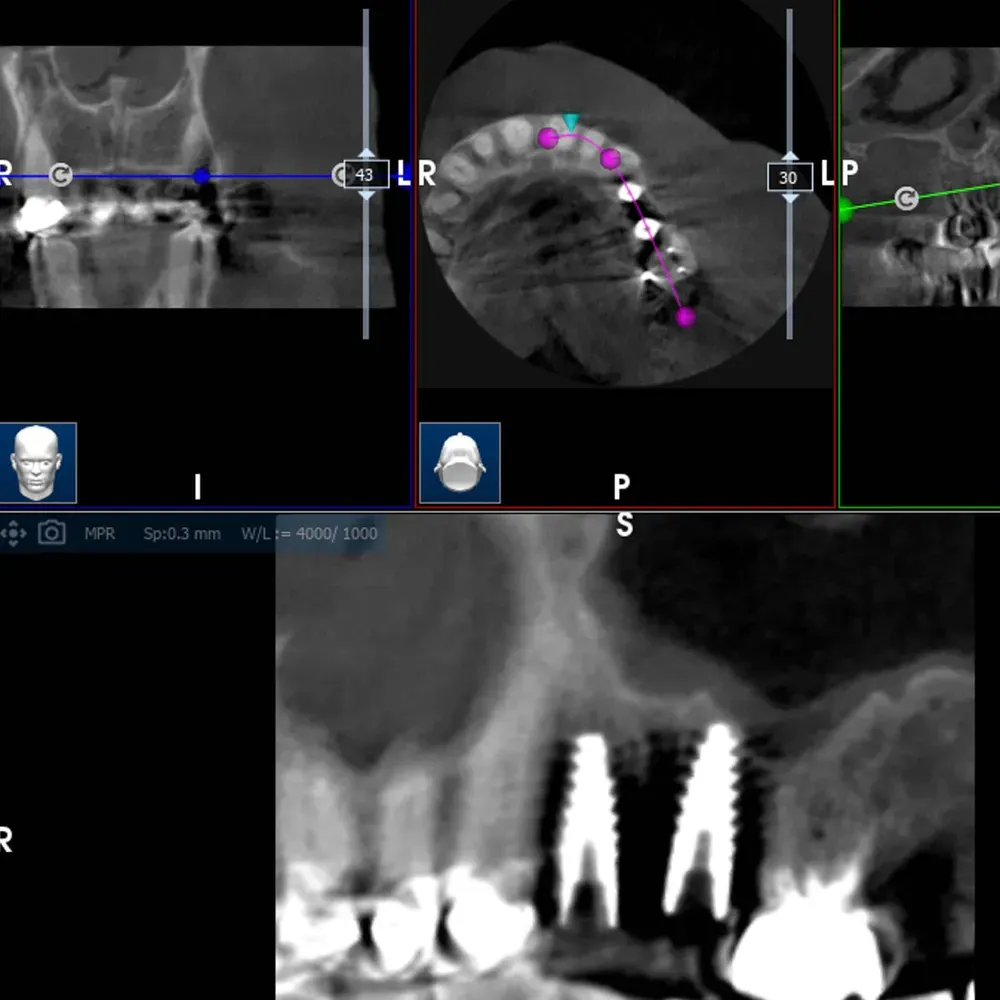

La CBCT dimostra l’anatomia atrofica della zona, con la vicinanza del pavimento del seno mascellare e la significativa perdita di sostanza palatale dovuta all’infezione parodontale.

CBCT di elemento dentario 2.5 affetto da carie e tasca parodontale acuta

CBCT dell’elemento 2.5 con evidenza della vicinanza del seno mascellare e della distruzione del parodonto, soprattutto sul versante palatino.

La CBCT intraoperatoria ha confermato la corretta posizione tridimensionale degli espansori e il raggiungimento della corticale del pavimento del seno in zona 2.5. In caso di dubbi sulla posizione e nel corso di interventi delicati come questo, questo ausilio strumentale è di fondamentale importanza. Ma non è sempre necessaria. L’esposizione, per quanto contenuta, dev’essere sempre ridotta al minimo, compatibilmente con la sicurezza chirurgica.

Visione laterale espansori

Sezione espansore sito 2.4

Sezione espansore sito 2.5

CBCT Post-op: Impianto in posizione 2.4 infracrestale che ha raggiunto la posizione di ingaggio corticale corretta

Espansore in posizione 2.5 con sollevamento della corticale del pavimento del seno

CBCT Post-op: Impianto in posizione 2.5 infracrestale con sollevamento della corticale del pavimento del seno